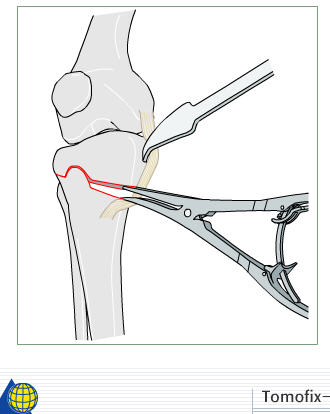

И зачем латерализация периферического фрагмента. Я всегда делаю медиализацию. См схему. И для данного случая медиализация подходит как нельзя лучше.

a> Я всегда делаю медиализацию. См схему. И для данного случая

Медиализация - это чисто эстетический прием, как я понимаю. Поскольку если делать остеотомию ниже вершины деформации, для восстановления оси надо делать смещение по ширине, в данном случае как раз латерализацию.

А вот на схемке без осей - там на разных уровнях (который правильнее?) устранение варуса чисто открытым клином без медиализации-латерализации. Если как-то так сделать - этого недостаточно будет?

Ещё картинка - схема. Хотя у Соломина всё написано.